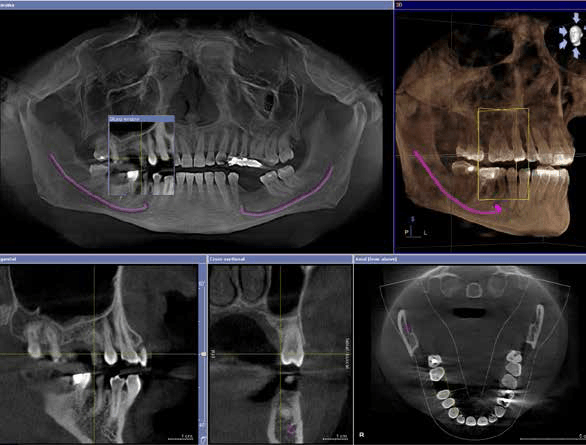

Inoltre lo studio è munito di un’apparecchiatura TC (Tomografia computerizzata) volumetrica con tecnologia CONE BEAM (CBCT) che permette di analizzare le strutture anatomiche nei tre piani dello spazio invece che bidimensionalmente (come nelle ortopantomografie). Questa tecnologia permette l’acquisizione di immagini estremamente accurate con una esposizione ai Raggi X nettamente inferiore rispetto ad una TC tradizionale. Da un punto di vista clinico l’acquisizione di queste immagini 3D si traduce in una riduzione al minimo della possibilità di errore nel piano di trattamento.

Pertanto nel caso di necessita di CBCT per motivi di implantologia, inclusioni dentarie, valutazione delle vie aeree ecc… il paziente la potrà eseguire direttamente e comodamente in studio.